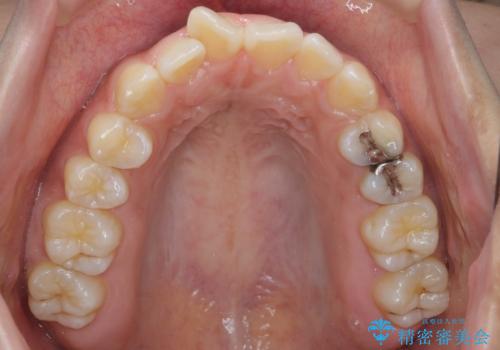

- 前歯の目立つねじれを矯正治療で治したい、と来院されました。

マウスピース矯正を始める前に、ねじれを取るのが短期間で済む部分ワイヤー小矯正を行うことで、全体的な治療期間を短くする治療計画を実行していきます。

前歯のねじれはマウスピース矯正の苦手な動きになり、治療期間が長くなる原因になりやすいです。